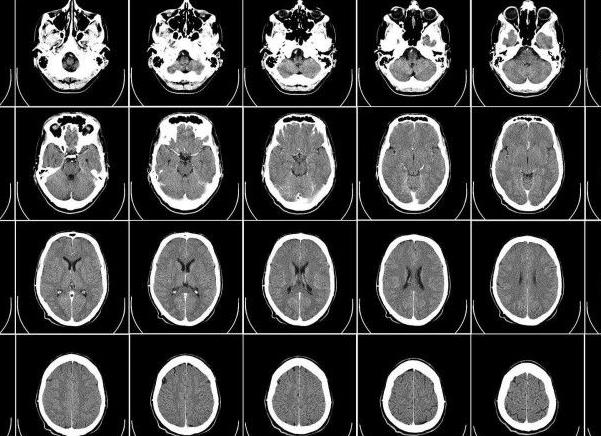

Существует два типа томографов: открытого типа и закрытого или туннельного. Закрытый томограф – это устройство, напоминающее огромную трубу. В нем создается магнитное поле и туда на специальном столе закатывается пациент. В связи с тем, что при определенных видах диагностики пациент находится в томографе довольно долго, он может испытывать дискомфорт от замкнутого пространства. Открытый томограф – это помещение, наподобие рентгеновского кабинета, в котором находится пациент. К нему в любой момент может подойти медсестра или кто-либо из родных. Это отличное изобретение для пожилых, очень больных пациентов или маленьких детей. К тому же, во время выполнения томограммы можно сразу же проводить какие-либо лечебные мероприятия. Томограф может очень четко показать вид головного мозга, спинного мозга, суставов, внутренних органов (кроме полых), органов малого таза. С помощью этого вида диагностики обнаруживаются опухоли, спинномозговые грыжи, нарушение строения или патологические процессы во внутренних органах. Томограф показывает орган в виде срезов. Таким образом, результат обследования – это большой лист, испещренный маленькими фотографиями каждого среза интересующего органа. Можно задать ширину среза – например, каждые два сантиметра. Очень хорошо различаются и ткани. То есть врач сразу поймет, с чем имеет дело: жировой прослойкой, осколком кости или полостью, заполненной жидкостью. Контрастное вещество используется при МРТ в тех случаях, если необходимо выявить опухоль, ее размеры, состав клеток и границы. Контраст позволяет более детально изучить структуру тканей. Контрастное вещество вливается внутривенно, это неопасно и практически безболезненно.

Для исследования разных органов, находящихся в области головы, используются разные режимы. Аппарат дает возможность детально изучить состояние орбиты глаз, тканей мозга, эпифиза, гипофиза, внутреннего уха, продолговатого и промежуточного мозга, а также мозжечка. Перед операцией на головном мозге также нередко назначается МРТ, позволяющая заранее спланировать ход операции, сделать ее наименее травматичной для пациента. С помощью этого метода можно эффективно продиагностировать состояние головного мозга, не нанося ущерб организму, в удобных для пациента условиях. При этом современные томографы дают очень высокое качество картинки. Из всех существующих методов обследования позвоночного столба этот наиболее современный и совершенный. В ходе обследуются все отделы позвоночника по очереди. Врач видит костные образования, сосуды, мягкие волокна, окружающие позвоночный столб, а также нервные окончания. Это дает возможность точно определить, что происходит в органе. За одно обследование можно получить полную информацию о состоянии межпозвоночных дисков, позвонков, корешков спинного мозга, оболочек и близлежащей мускулатуры.